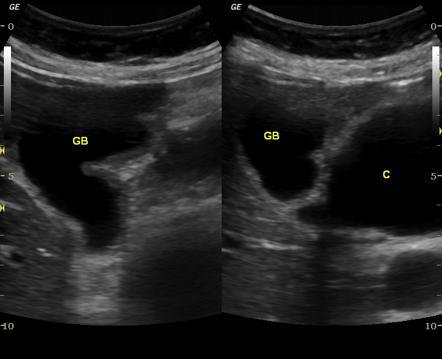

Pancreatic Psydocyst

Spherical fluid collection of pancreatic enzymes that arise from inflamatory, necrotic and hemorrhage processes of the pancrreas

persistently elevated amylase and lipase

Pancreatic Psydocyst

Spherical fluid collection of pancreatic enzymes that arise from inflamatory, necrotic and hemorrhage processes of the pancrreas

persistently elevated amylase and lipase

Pancreatic Psydocyst

Spherical fluid collection of pancreatic enzymes that arise from inflamatory, necrotic and hemorrhage processes of the pancrreas